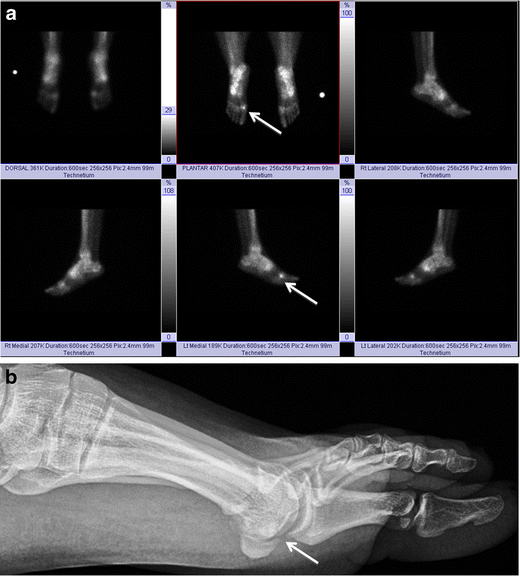

Sesamoiditis. Bone scan of the bilateral feet (a) in a patient with plantar foot pain reveals nonspecific but intense tracer uptake localising to the medial hallucal sesamoid. AP radiograph at the first toe (b) reveals a bipartite medial hallucal sesamoid with no diastasis, fragmentation or sclerosis. The patient was diagnosed with bony sesamoiditis

Osteoarthritis. Bone scan of the bilateral feet (a) shows nonspecific but intense tracer uptake localising to the medial hallucal sesamoid (arrows). Lateral radiograph at the first toe (b) reveals joint space narrowing and osteophyte formation at the medial sesamoid-metatarsal articulation (arrow), consistent with osteoarthritis

Compared with the aforementioned ossicles, the os intermetatarseum is less commonly reported as a cause of pain. However, compression of the superficial or deep peroneal nerve by this ossicle has been described as a source of dorsal foot pain [13, 30]. Patients present with pain and/or numbness at the dorsum of the foot that is exacerbated by standing or jumping, and tenderness to palpation at the first intermetatarsal interspace [13, 30]. Scintigraphy may reveal increased radiotracer uptake in a symptomatic os intermetatarseum [13].